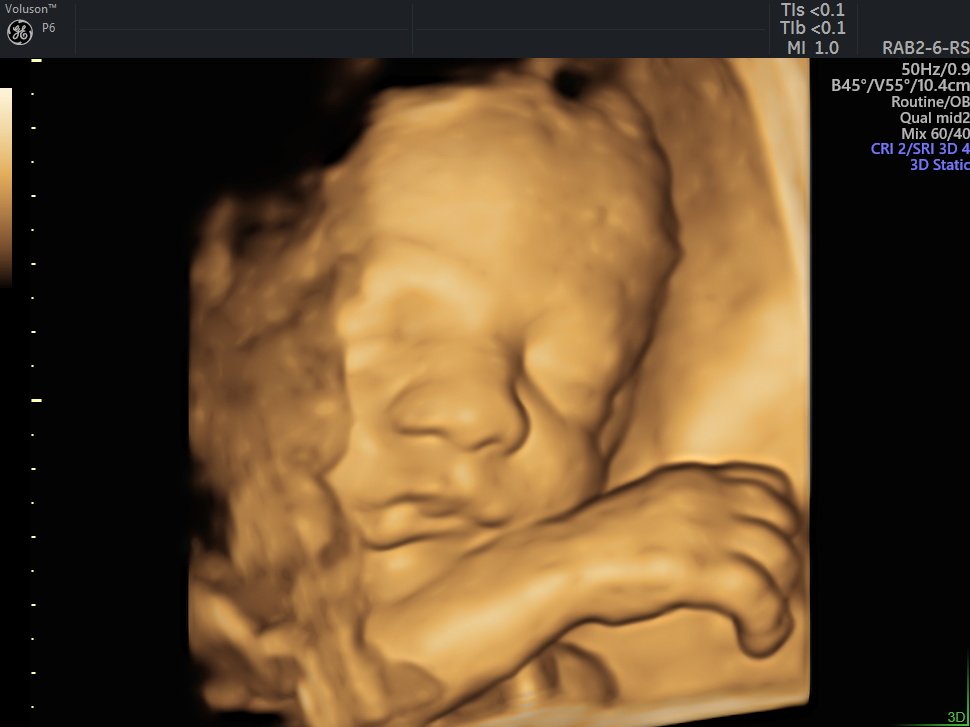

4 Boyutlu (Renkli) Ultrason ve Doppler Ultrasonografi

4 D Ultrasonografi